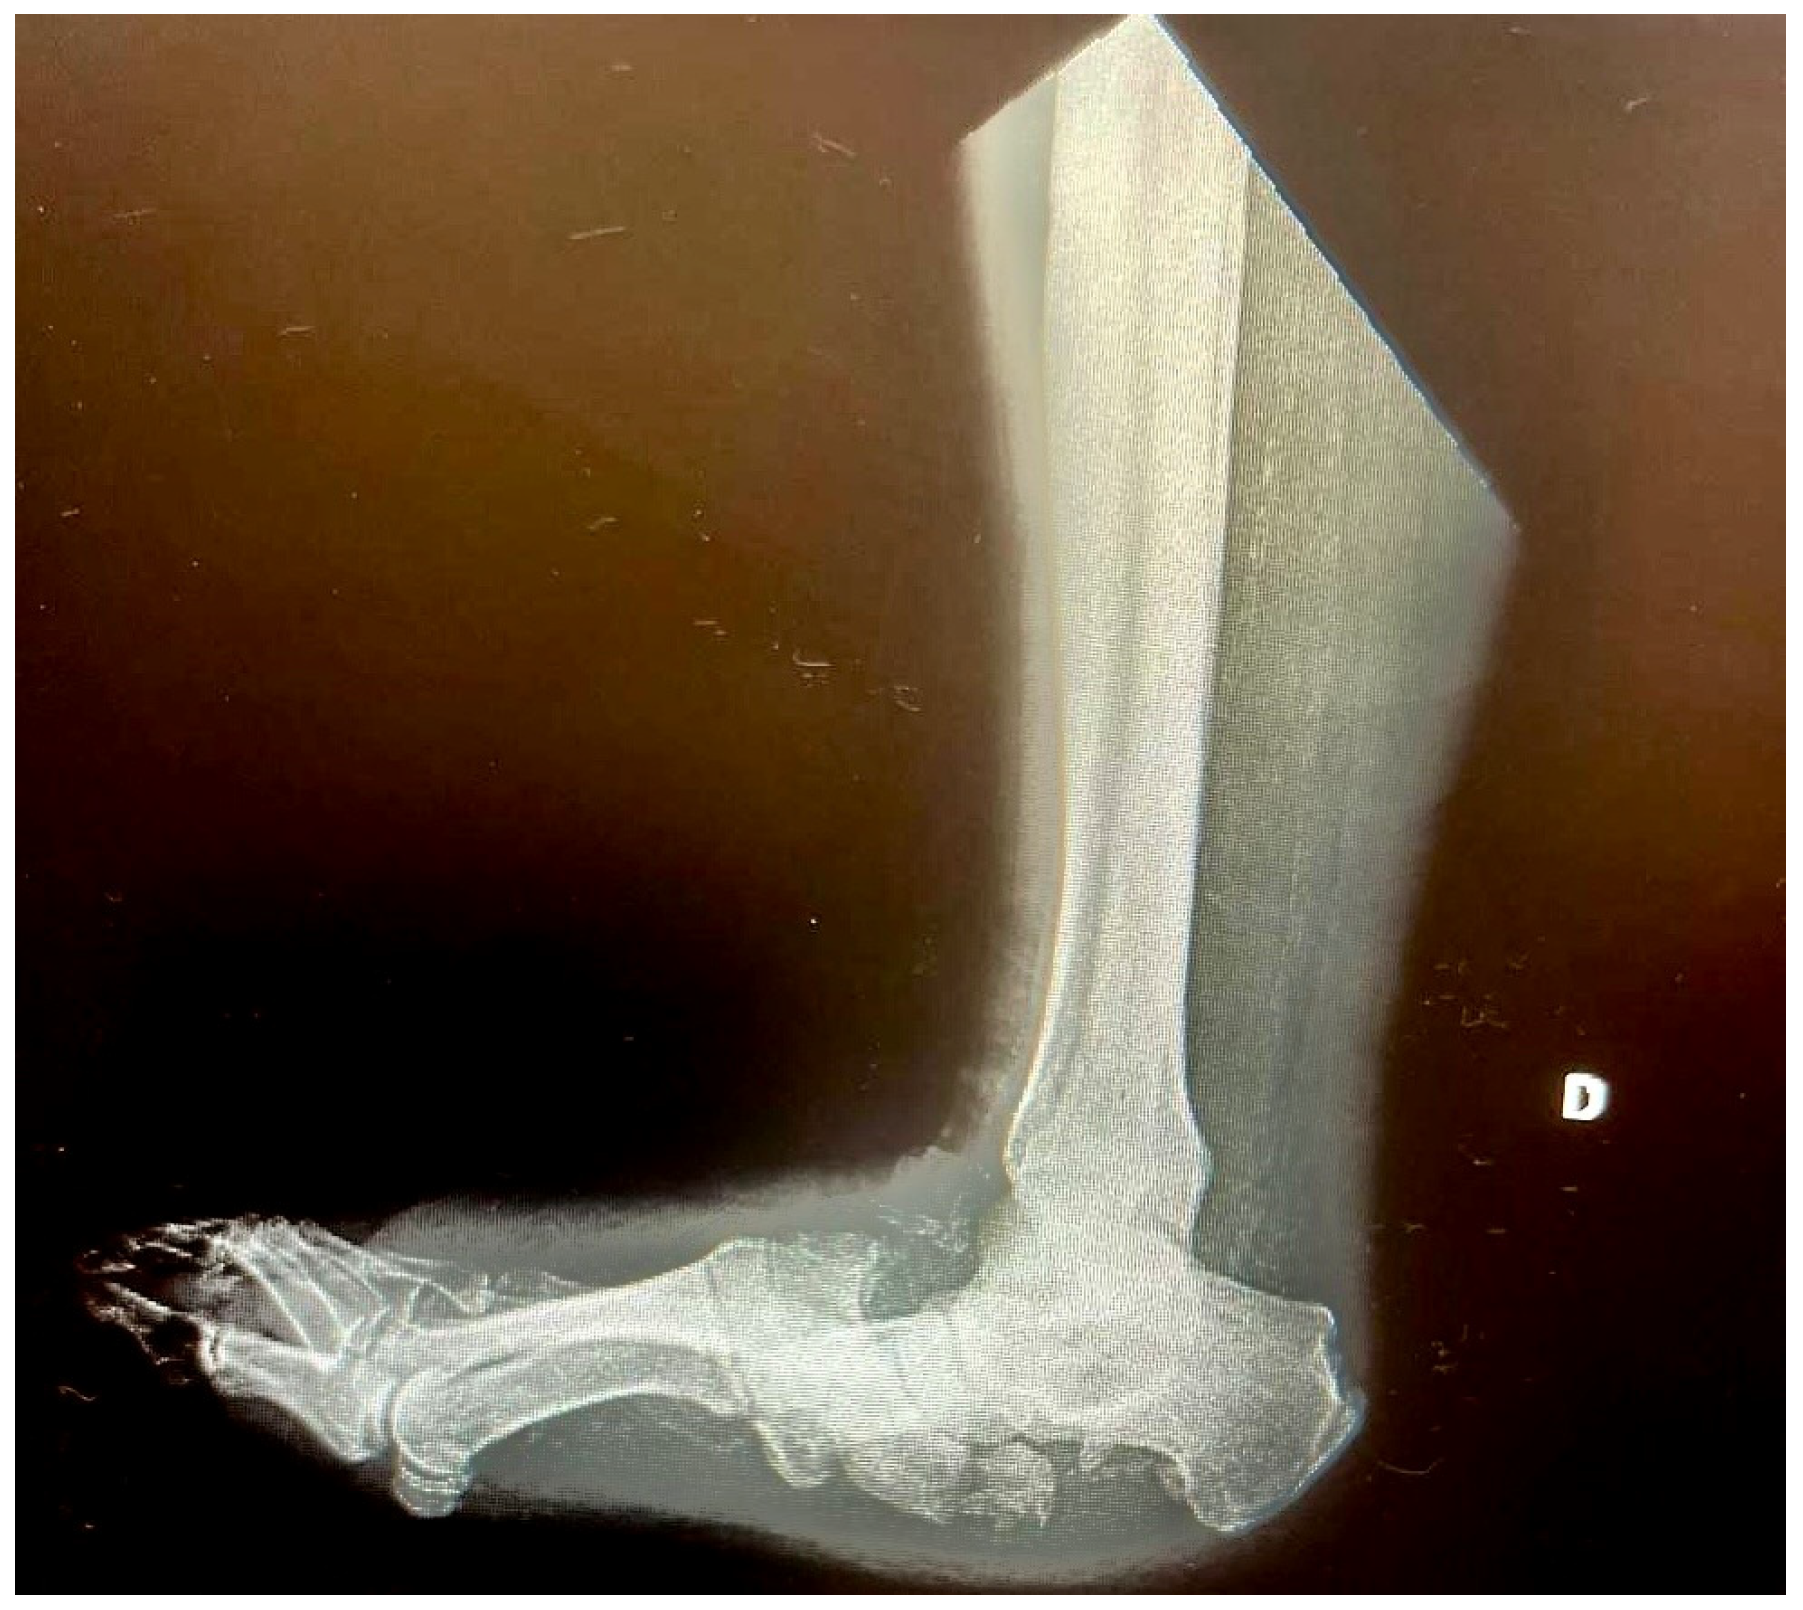

3. X-Rays